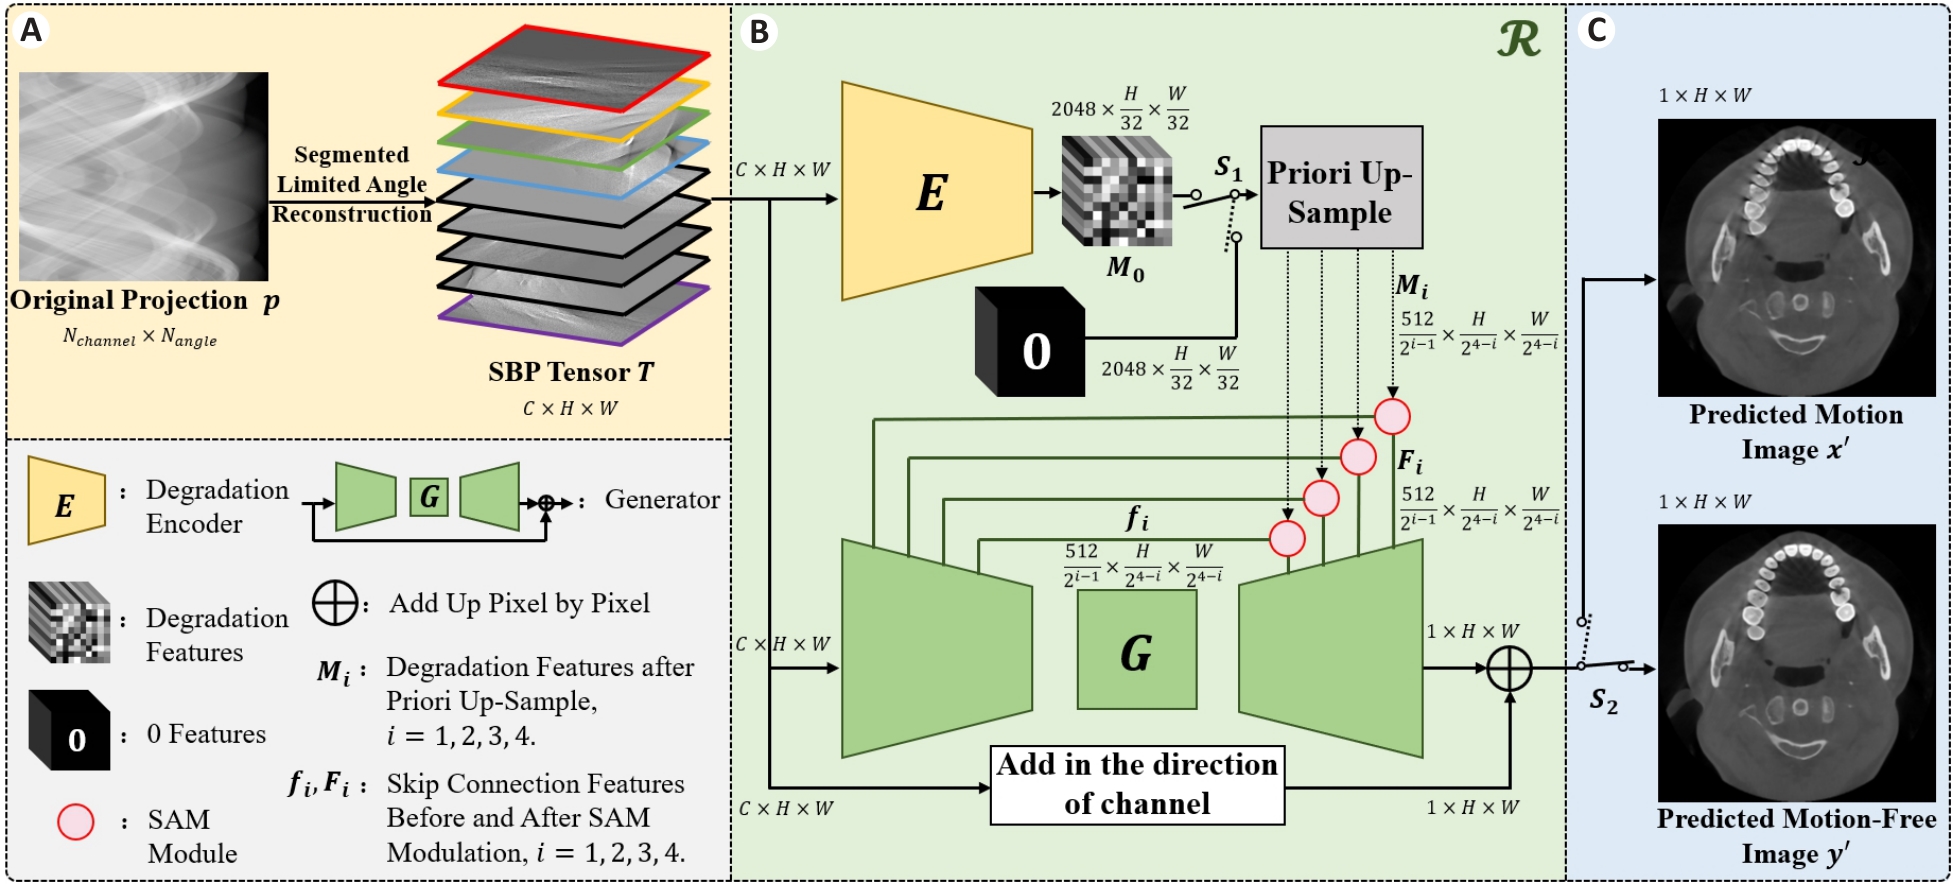

Fig.2 Flow chart of the SBP-MAC model. A: Preparation of the input data of the model. B: Composition of the proposed model. C: Output results of the model.